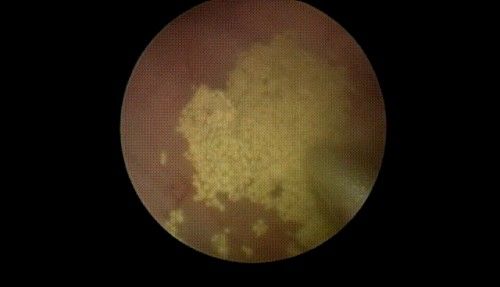

拥有无比清晰的视野,再小的结石也无所遁形

看,这就是公猫常见的结晶堆,细如沙粒,如果没有膀胱镜,这只喵喵可要遭大罪了呢~

结晶堆

在火眼金睛的加持下,任凭你们或来势汹汹,都挡不过微创大军的全面进攻!配合着吸石泵等工具下,功夫不负有心人,李韶清医生把膀胱清得一干二净。